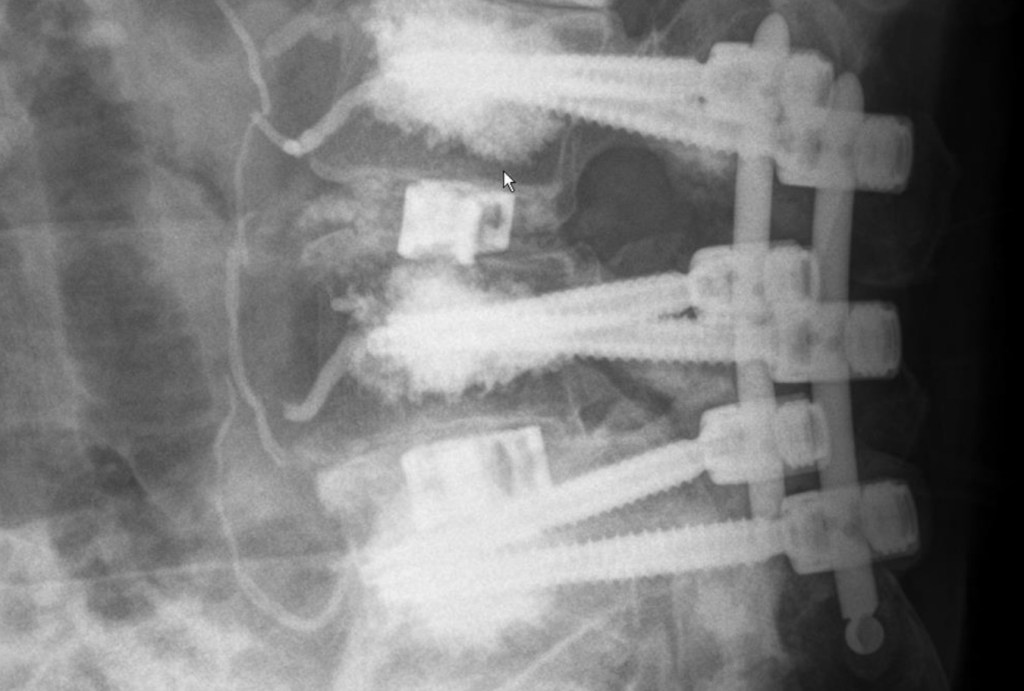

Fifteen years ago, I tell them,I was invincible, nothing bothered me,nothing held me back and eventhe few surgeries were shortrest stops on a runner’s highway. I knew it would last forever, Iknew I was kidding myself. Now, aging, I am held togetherby titanium and injections,trying to fall apart withas much grace as possible. My little…